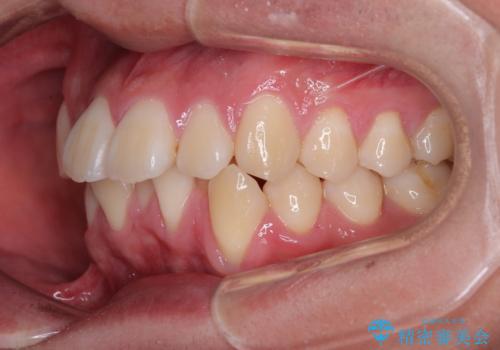

- 全顎的なデコボコを気にして来院された患者様です。

特に前歯のデコボコが顕著であり、上下左右第一小臼歯の4本を抜歯し、ワイヤー装置を使用して咬み合わせ高さを改善しながら、歯列を整えて行くこととしました。